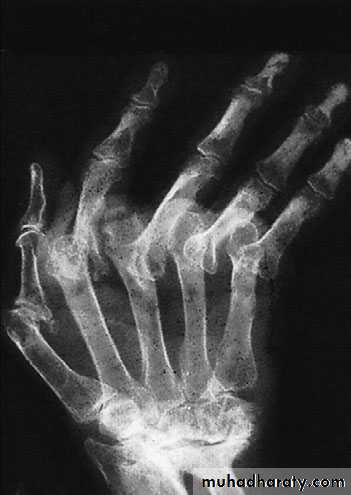

RHEUMATOID ARTHRITIS

X-ray:

most common sites:(MCP) joints, the wrists and

distal (RA) jointsPATHOLOGY:

Synovitis of the joints and tendon sheaths

the disease joints become eroded

attenuation of the ligaments and tendons

instability and progressive deformity

tendon rupture

Clinical features:

Stiffness and swelling of the fingers

carpal tunnel compression

swelling of the MCP and PIP joints, giving the fingers a spindle shape;

Bilateral symmetrically.

The joints are tender and crepitus may be felt on moving the tendons.

grip strength are diminished.

Early deformity : slight radial deviation of the wrist and ulnar deviation of the fingers, correctable swanneck deformities of some fingers, an isolated boutonnière or the sudden appearance of a drop-finger or mallet thumb (from extensor tendon rupture).

Late deformity: the carpus settles into radial tilt and volar subluxation; there is marked ulnar drift of the fingers and volar dislocation of the MCP joints, often associated with multiple swan-neck and boutonnière deformities.